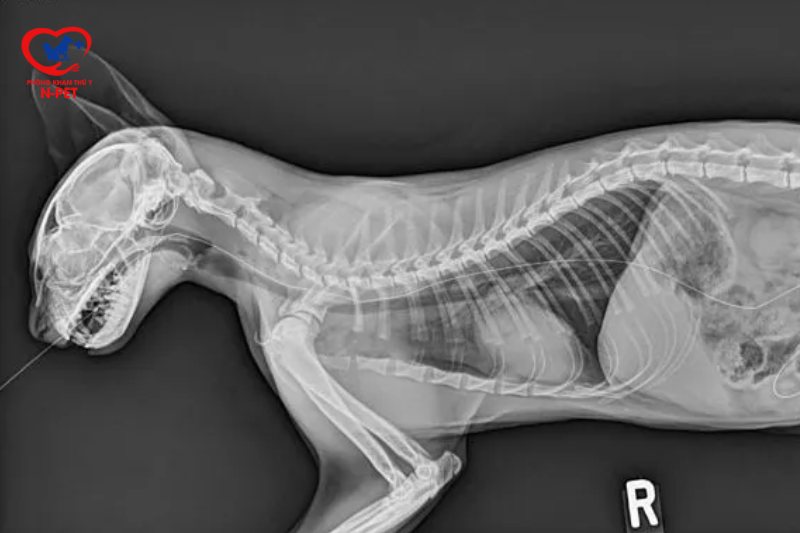

Khi mèo của bạn có dấu hiệu bị bệnh, việc chụp X-quang có thể là một bước đi cần thiết. Đây là một công cụ chẩn đoán quan trọng giúp bác sĩ thú y xác định những vấn đề nghiêm trọng như gãy xương, sự hiện diện của dị vật trong cơ thể hoặc các bệnh lý liên quan đến hô hấp. Nếu mèo bạn bị khó thở, chụp X-quang có thể giúp phát hiện ra nguyên nhân phát sinh những triệu chứng đó, chẳng hạn như bệnh tim hay tình trạng phổi.

Chụp X-quang cho mèo là một bước quan trọng trong việc chẩn đoán các vấn đề về sức khỏe, đặc biệt là khi nghi ngờ có gãy xương hoặc chấn thương. Quy trình này giúp bác sĩ thú y đánh giá tình trạng cơ xương và khớp của thú cưng, từ đó đưa ra những quyết định điều trị chính xác.

Trong quá trình chụp X-quang, mèo sẽ được đặt trên bàn chụp, ở một vị trí nhất định để đảm bảo hình ảnh rõ ràng nhất. Để có được hình ảnh chất lượng cao, bác sĩ thường sử dụng công nghệ chụp X-quang kỹ thuật số. Điều này không chỉ giúp đạt độ phân giải tốt mà còn giảm thiểu thời gian chờ đợi cho chủ nuôi.

Trong một số trường hợp, như khi mèo nuốt phải dị vật, bác sĩ có thể yêu cầu chụp X-quang với chất cản quang để quan sát đường tiêu hóa. Thăm khám lâm sàng toàn diện trước khi chụp cũng là một bước cần thiết để xác định chính xác những vấn đề mà thú cưng đang gặp phải. Tuy nhiên, để đảm bảo mèo không cử động trong quá trình chụp, thường cần phải sử dụng thuốc an thần hoặc gây mê.